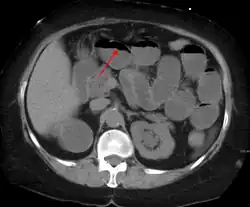

A small bowel obstruction as seen on CT

Causes of bowel obstruction include adhesions, hernias, volvulus, endometriosis, inflammatory bowel disease, appendicitis, tumors, diverticulitis, ischemic bowel, tuberculosis and intussusception.[1][2] Small bowel obstructions are most often due to adhesions and hernias while large bowel obstructions are most often due to tumors and volvulus.[1][2] The diagnosis may be made on plain X-rays; however, CT scan is more accurate.[1] Ultrasound or MRI may help in the diagnosis of children or pregnant women.[1]

Radiological signs of bowel obstruction include bowel distension (small bowel loops dilated >3 cm) and the presence of multiple (more than 2) air-fluid levels on supine and erect abdominal radiographs.[16] Ultrasounds may be as useful as CT scanning to make the diagnosis.[17]

Contrast enema or small bowel series or CT scan can be used to define the level of obstruction, whether the obstruction is partial or complete, and to help define the cause of the obstruction. The appearance of water-soluble contrast in the cecum on an abdominal radiograph within 24 hours of it being given by mouth predicts resolution of an adhesive small bowel obstruction with sensitivity of 97% and specificity of 96%.[18]